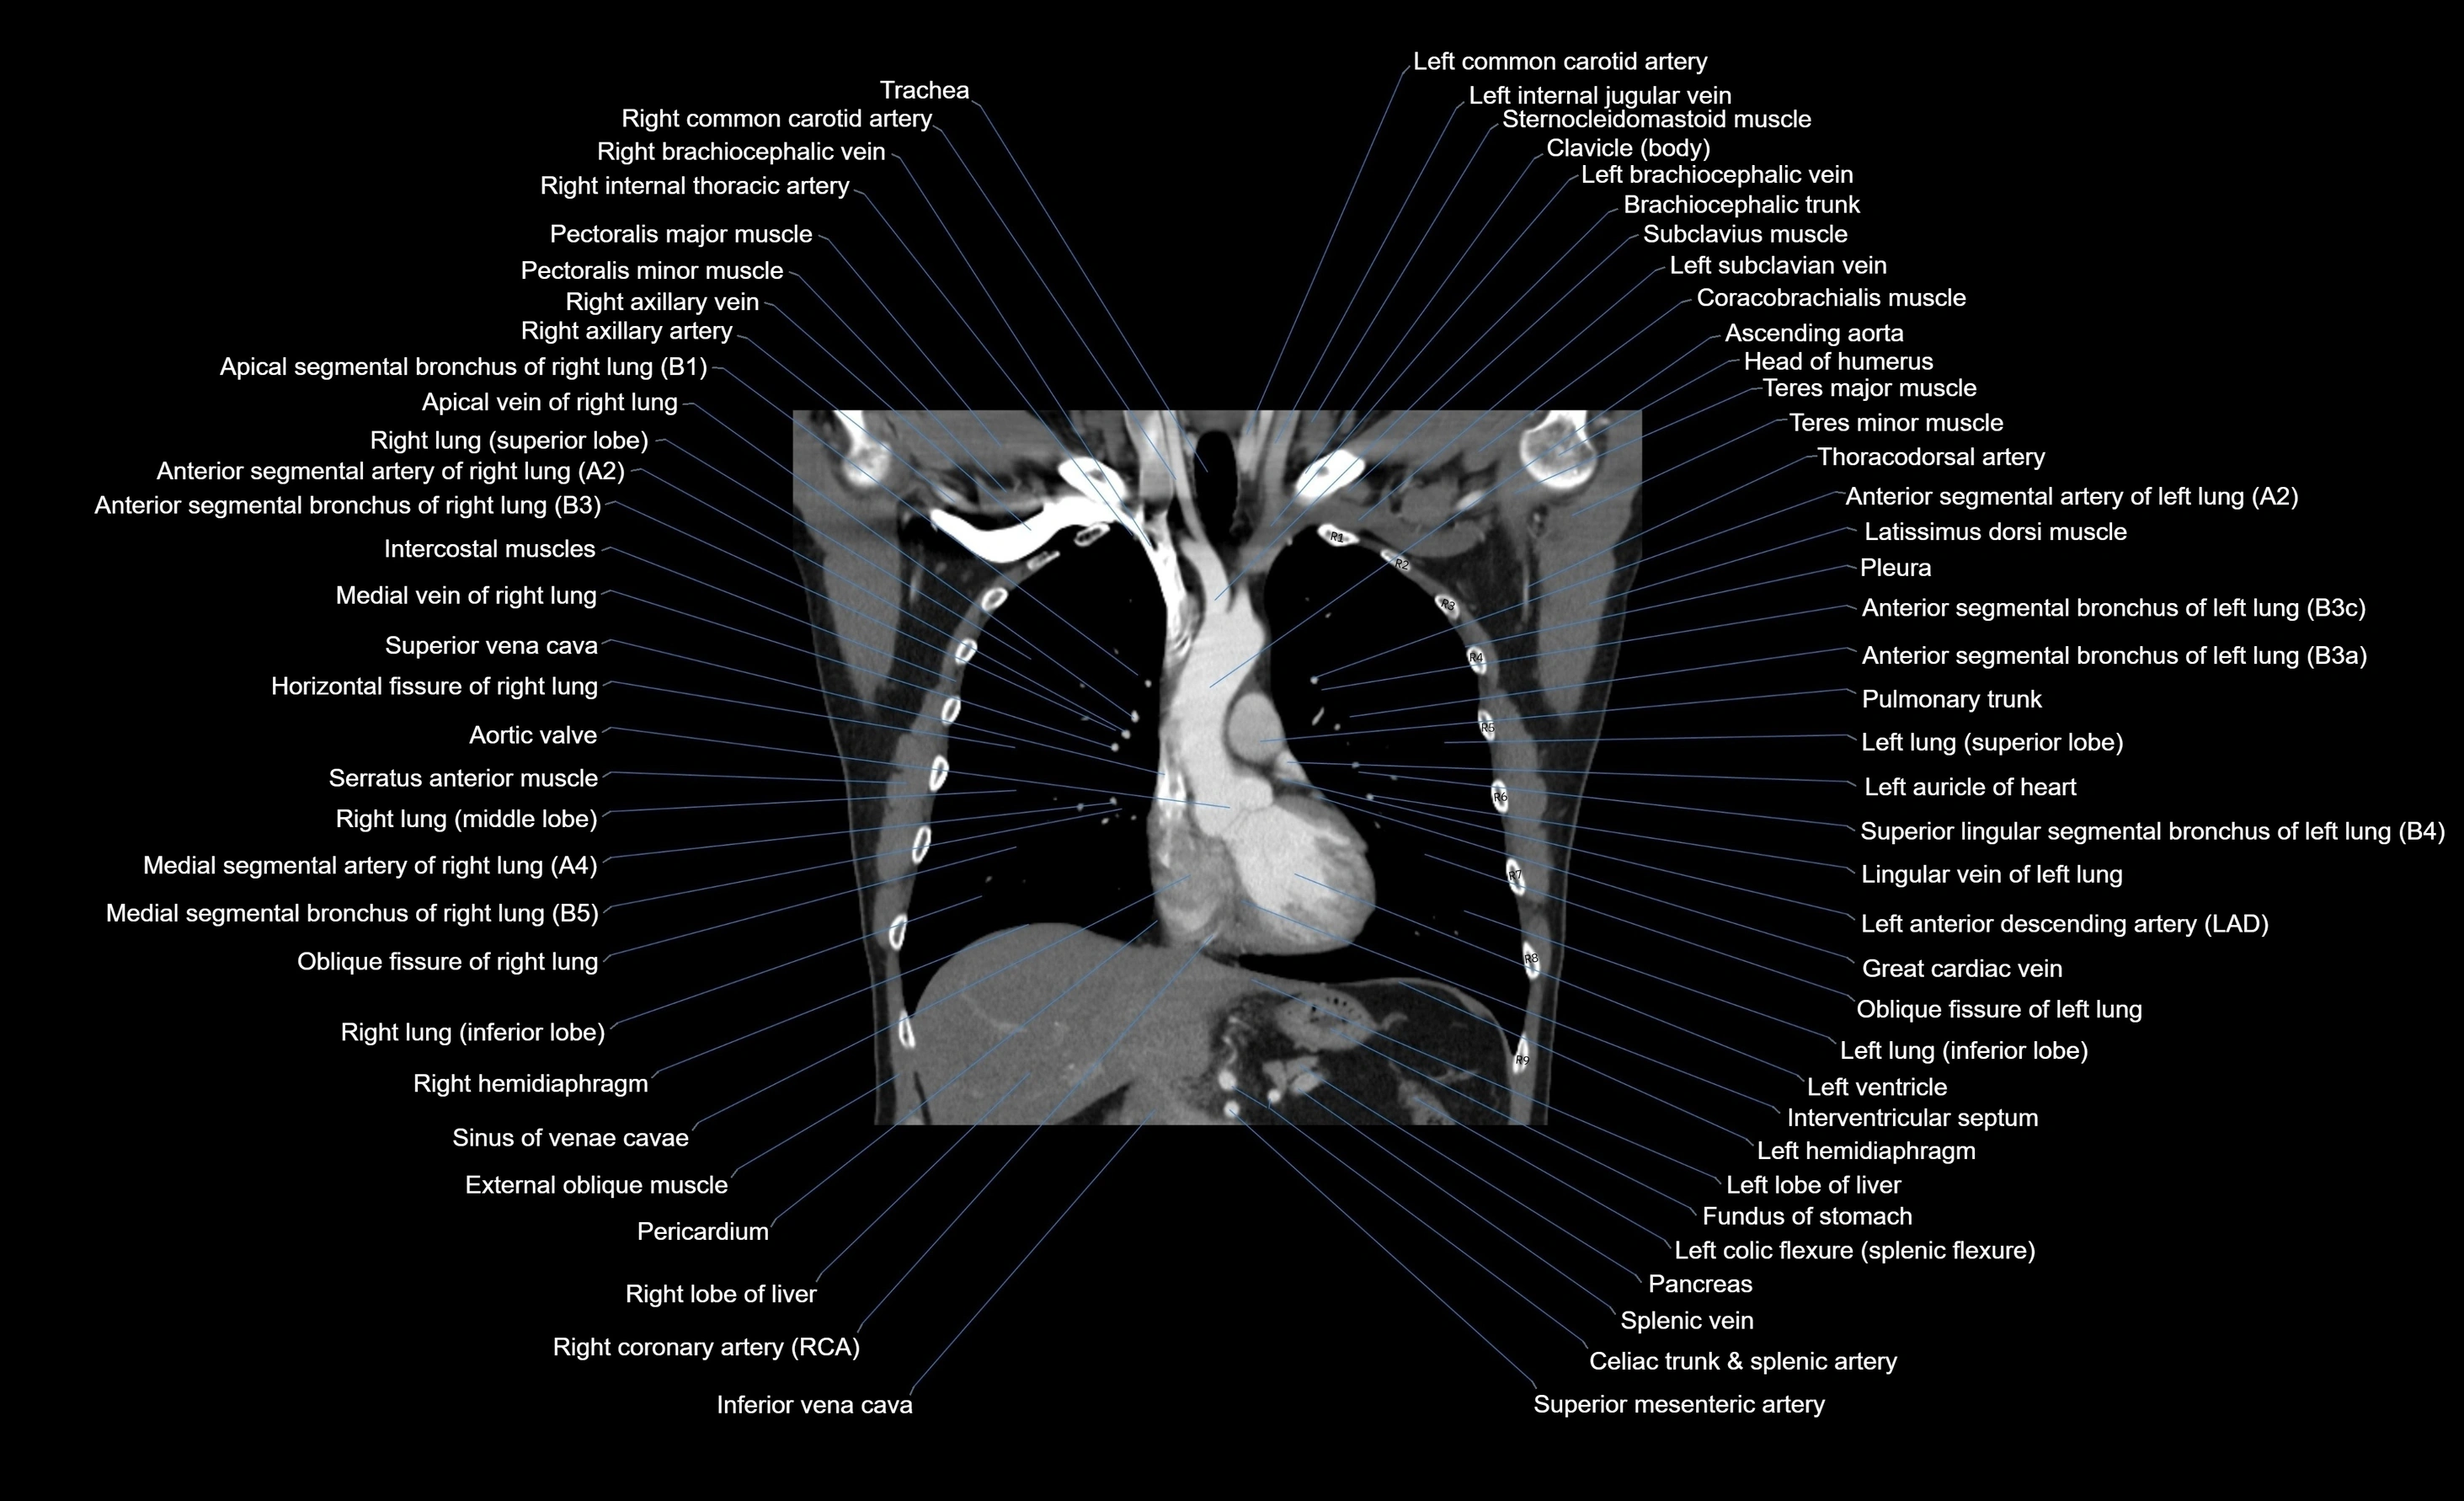

CT images